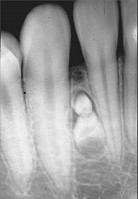

2.組圖為牙瘤的外觀及X 線表現,有關此病的描述錯誤的是  (    )

正確答案:E